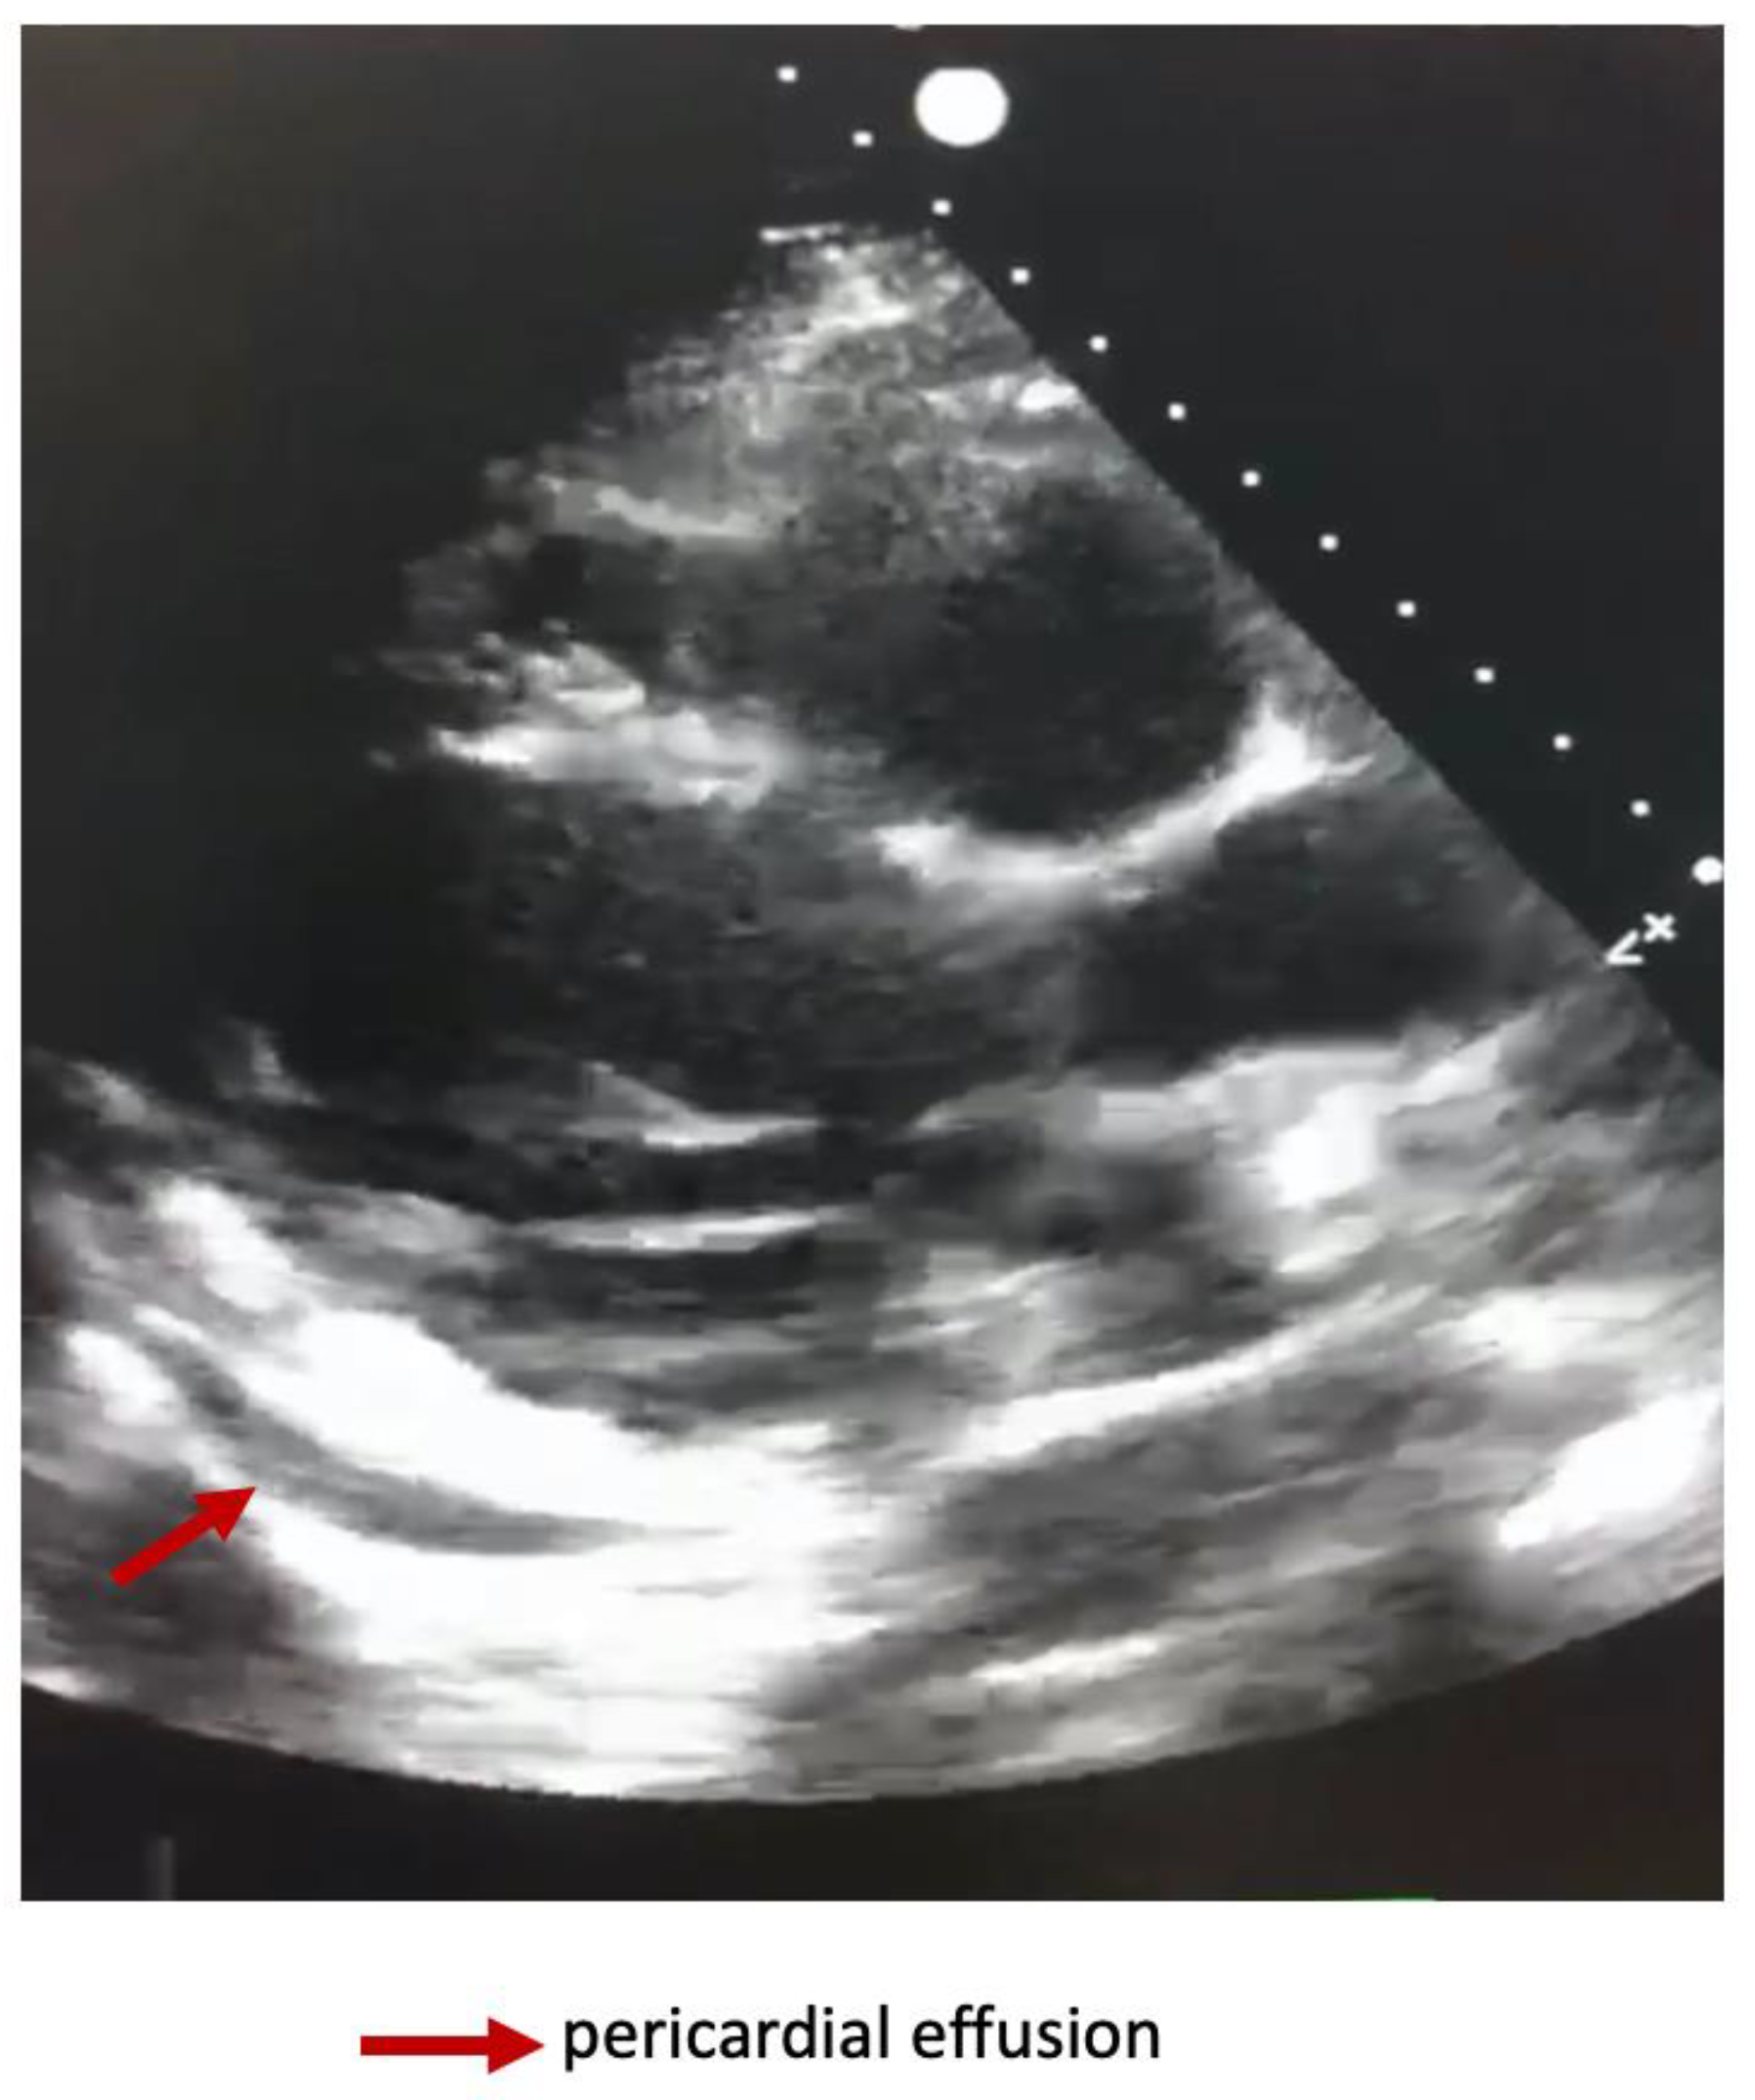

Repeated thoracic CT displayed significant circumferential pericardial effusion adjacent to the left ventricle and minimal bilateral pleural effusion (Figure 1).

Figure 1. Thoracic CT showing circumferential pericarditis.